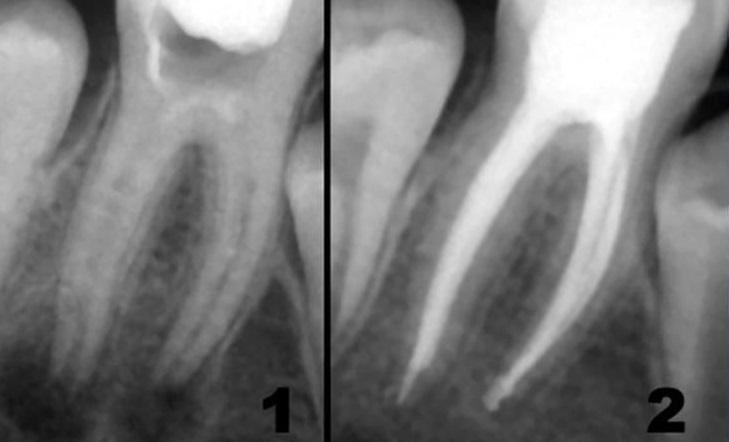

Рентгеновские снимки кариеса корня зуба

Раздел: Визуальные уроки